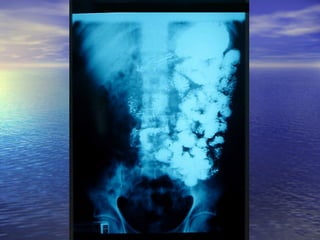

• 1.- Calibre de la luz intestinal1.- Calibre de la luz intestinal

• 2.- Contornos Superficie de mucosa2.- Contornos Superficie de mucosa

• 3.- Grosor de la pared de la mucosa3.- Grosor de la pared de la mucosa

• 4.- Desplazamiento de asas4.- Desplazamiento de asas

• 5.- Floculación, segmentación,5.- Floculación, segmentación,

obstrucciónobstrucción (Yeyuno imagen = pluma de(Yeyuno imagen = pluma de

aves)aves)

(ileon imagen = pila de monedas)(ileon imagen = pila de monedas)